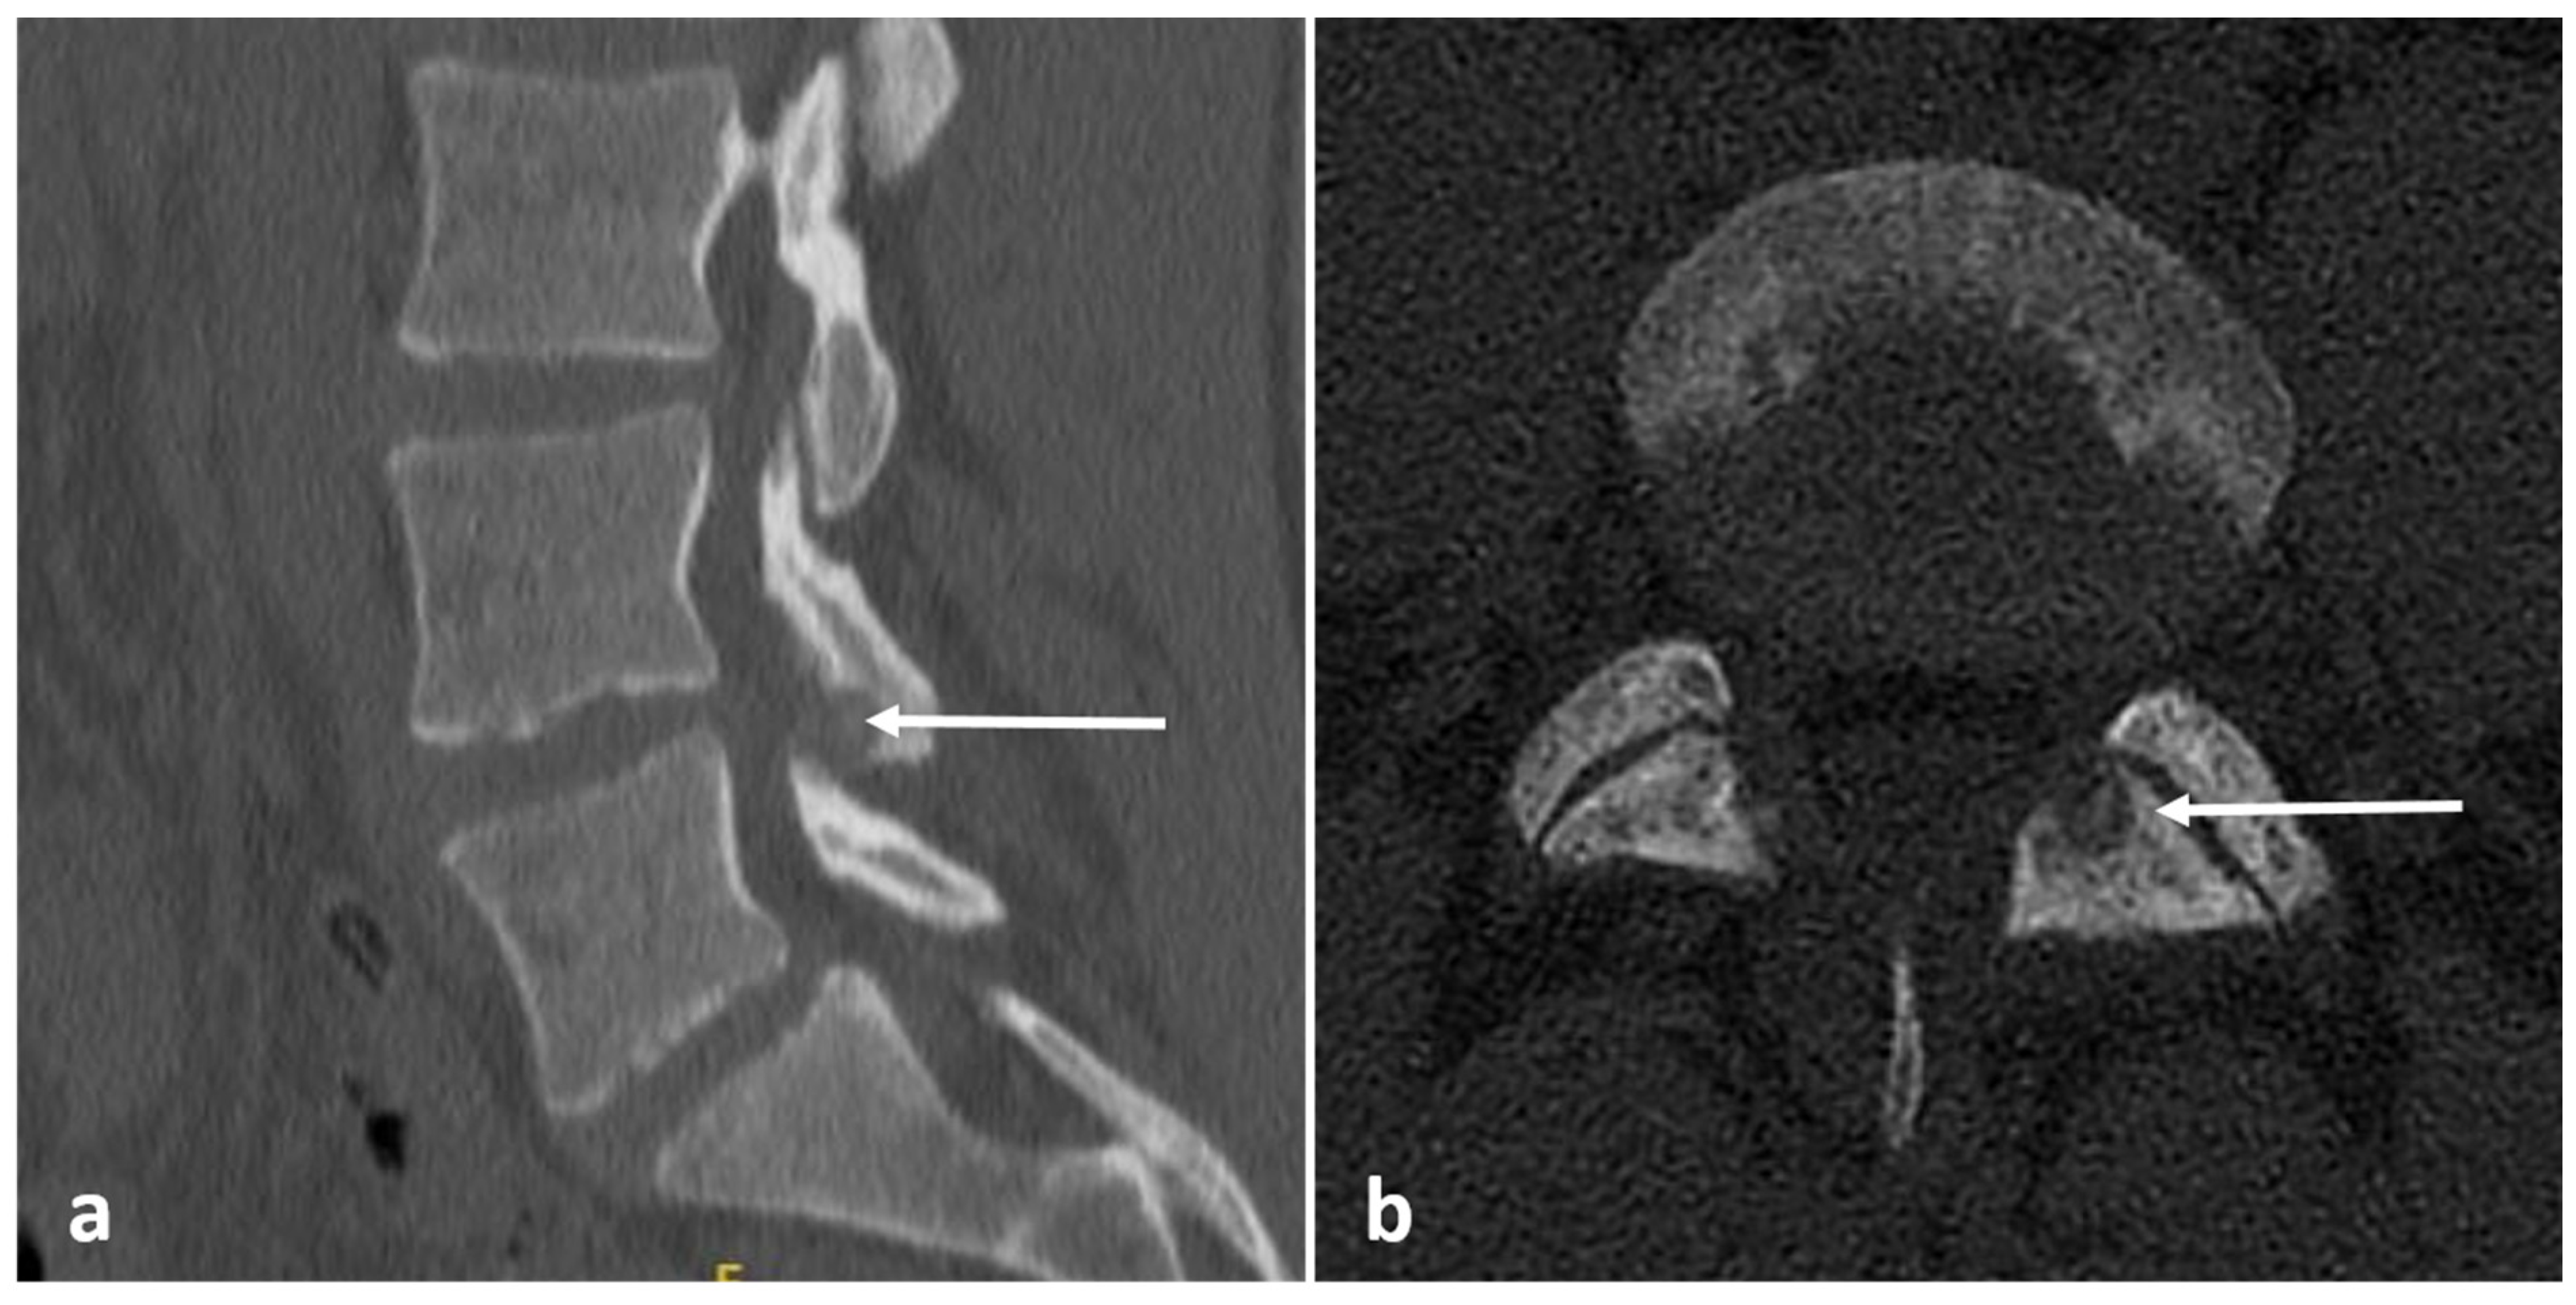

| Osteochondroma | Lesion continuity with cortex and medulla. | Cartilage cap |